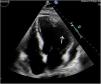

Paciente varón de 68 años que ingresa en la unidad de cuidados intensivos por infarto agudo de miocardio inferoposterolateral evolucionado KillipIV. En coronariografía emergente, enfermedad arterial coronaria severa de dos vasos tratada con angioplastia y stents farmacoactivos. Asocia disfunción ventricular moderada, hepatitis isquémica y necesidad de terapia de sustitución renal. En ecocardiografía transtorácica de control se objetiva aneurisma lateral (fig. 1, flecha blanca). Se completó estudio 7días después con resonancia magnética cardiaca (figs. 2-3). Objetivó pseudoaneurisma gigante de 90×60mm (flecha negra) con disfunción ventricular severa. Un cuello muy ancho (a favor de aneurisma), pero sin visualizar espesor miocárdico en la lesión, y con rápida expansión en una semana (a favor de pseudoaneurisma). En el centro de referencia se confirmó el diagnóstico y se inició estudio pretrasplante.